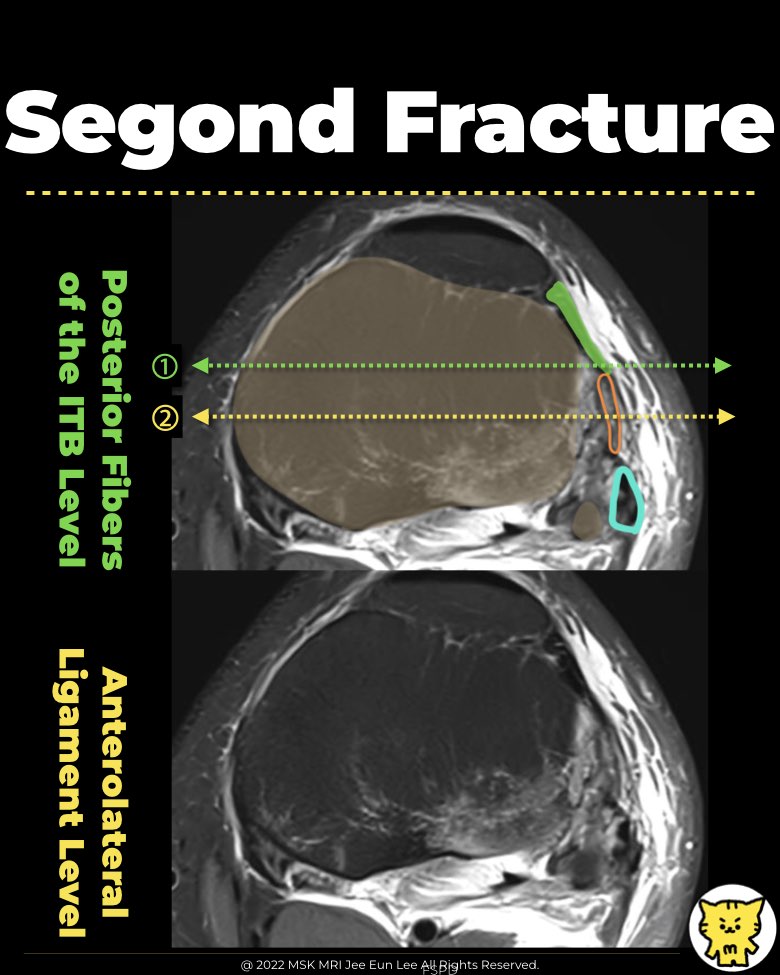

- In a study by Claes et al. (2017), the posterior fibers of the iliotibial band (ITB) and the lateral capsule (the anterolateral ligament) were found to attach to the Segond fracture fragment in 94% of patients.

- Caterine et al. (2016) reported that while MRI was unable to identify a distinct ligamentous attachment, the Segond fracture occurred at the location of the tibial insertion of the ALL, as described in the literature.

- Both the ITB and the ALL may be involved in the Segond avulsion, while the anterior arm of the biceps femoris tendon is not typically involved (Skeletal Radiol. 2015).